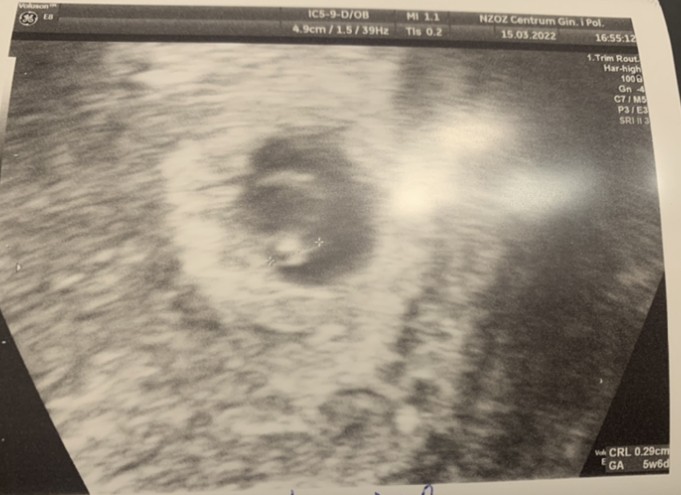

To jest tak trochę słabo tak mi się wydaje . Niby rośnie.. ale jednak są to małe wartości, według OM wychodzi 5 tydzień, natomiast od domniemanej daty poczęcia zaledwie 3 tygodnie...